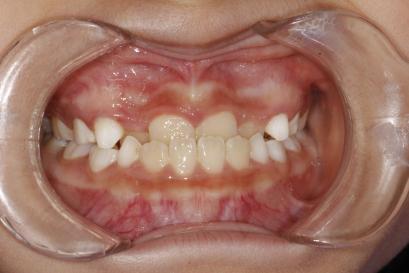

案例二:

治疗前

治疗后